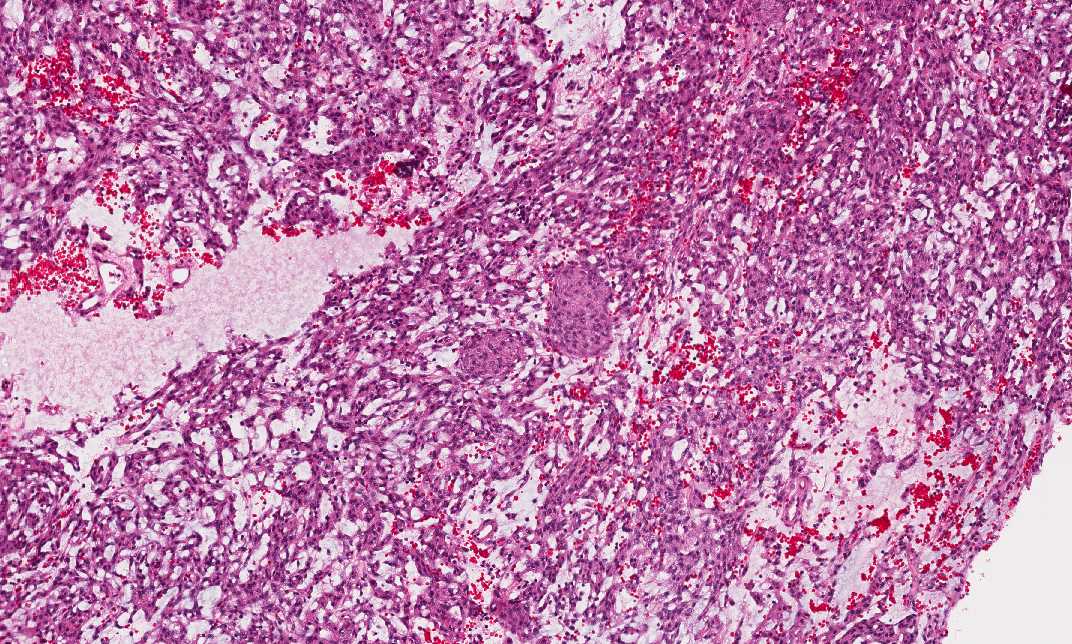

Hematoxylin & eosin

Area 2: This area has substantial amount of intercellular mucoid material in between tumor cells. It looks quite different from Area 1. However, if you put in some imagination and mentally add the intercellular mucoid material to Area 1, the two areas do not look that much different anymore.

Area 3: In this area, there are some islands that are suggestive of meninogthelial meningioma component. If you pay attention, however, these cells also have fine bubbly cytoplasm.

• In other areas (Area 2 and 3), however, substantial amount of mucoid material is present in between the tumor cells. Also, the cytoplasm is more bubbly in these areas. The mucoid material is well demonstrated with Alcian blue stain.